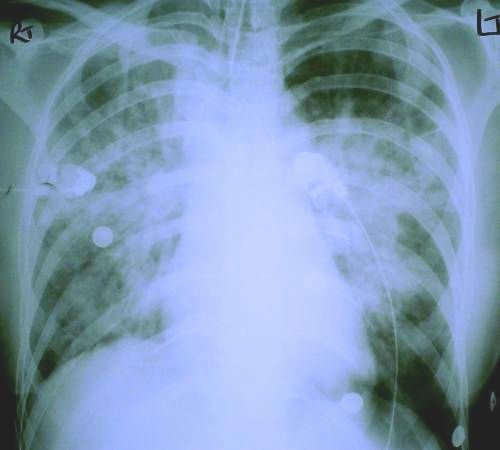

linear skin abrasion following attempted hanging A young woman was admitted to ICU after an attempted hanging. The neck abrasion present on admission is shown in the above photograph. There was no evidence of cerebral ischaemic or hypoxic damage, cervical spine injury, or carotid artery lesions. The following picture shows her initial chest x-ray, taken shortly after admission.

initial chest x-ray

.. and a chest x-ray taken several hours later..

subsequent chest x-ray

The question is, what caused the bilateral pulmonary infiltrates that blossomed in her lungs?